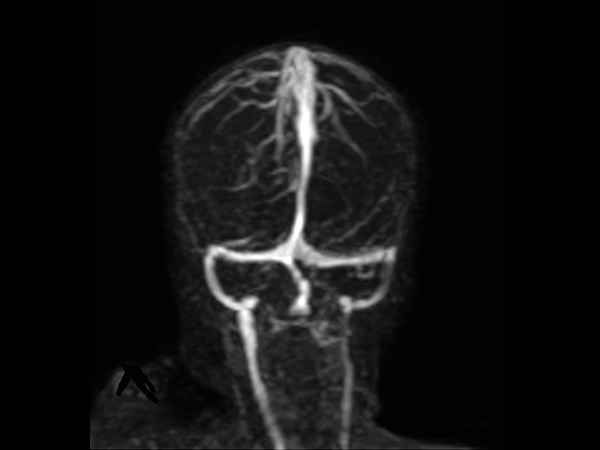

Coronal 3D TOF (MIP)